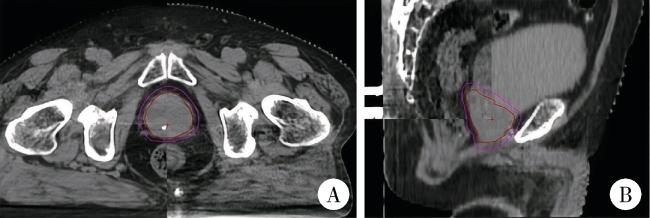

使用截石位碳纤维全身固定架固定体位的患者定义为A组,膝托仰卧,双臂上台交叉置于头顶,平躺于特制体架上,双腿放置于腿架内,根据激光灯在患者皮肤表面标记十字线,并记录与体架刻度线的对应位置(图 1A)。

图1 前列腺癌放射治疗体位固定装置

Figure 1 Positioning and fixation devices for prostate cancer radiotherapy

A, a carbon fiber whole-body fixator in lithotomy position; B, a conventional carbon fiber human body fixator and thermoplastic film.

使用常规碳纤维人体固定架的患者定义为B组,采取仰卧位,下肢伸直,双手上举并抱肘至额头位置,通过低温热塑膜固定体位,随后选择中心点,记录体架刻度线与体模激光灯十字线的对应关系(图 1B)。